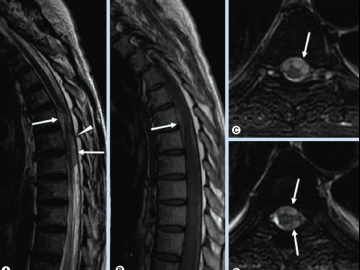

МРТ при межреберной невралгии назначает сделать невролог, когда необходимо определить, какие нервные окончания защемлены и дают боль в груди. Визуализировать все позвоночные структуры грудины можно на МРТ грудного отдела позвоночника. Если боль при межреберной невралгии отдает как в ребро, так и в шею, потребуется сделать комплексную МРТ шеи и грудного отдела позвоночника, чтобы точно разобраться в причинах торакалгии.

МРТ при межреберной невралгии

Точно установить причину межреберной невралгии и дифференцировать ее от кардиологических заболеваний врачам помогает МРТ грудного отдела позвоночника. Магнитно-резонансная томография грудного отдела позвоночника – наиболее надежный и информативный метод обследования мягких и костных тканей позвоночника. Она не требует хирургического вмешательства и, в отличие от рентгена и КТ, выполняется без применения вредного для человека излучения.

Признаки межреберной невралгии на МРТ

На МРТ снимках межреберная невралгия проявит себя следующими признаками

- давление корешков нервных окончаний;

- наличие воспалительных тканей по ходу движения нервов;

- четкий первоисточник зажима.

Компьютерная томография более информативна для выявления патологический костной ткани, этот метод диагностики часто сочетают с миелографией. Миелография проводится с применением контрастного вещества, его вводят в спинномозговой канал для исследования спинного мозга и нервных корешков. К современным, высокоинформативным методам исследования относится магнитно-резонансная томография. Диагностика основана на получении изображения органов и тканей при помощи электромагнитных волн. Методом МРТ выявляют патологические изменения мягких тканей (нервных структур, мышц, связок).